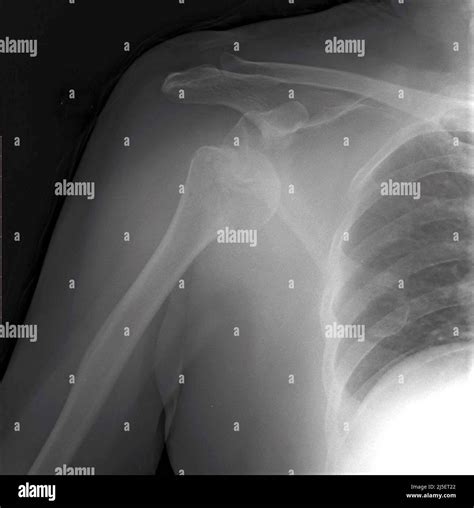

• Visualizing the position of the bones: It confirms whether the humerus is truly out of the socket or if there is a partial dislocation (subluxation).

• Assessing alignment: It helps doctors identify the specific type of dislocation—whether it is anterior (forward), posterior (backward), or inferior (downward).

• Anteroposterior (AP) View: Taken from the front, this view helps doctors see the general relationship between the humerus and the socket.